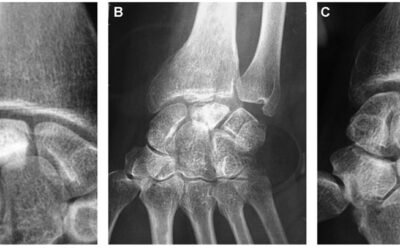

Em 1910, Preiser descreveu a necrose avascular do osso escafóide, que ficou conhecida como Doença de Preiser. Coincidentemente, no mesmo ano, Kienböck descreveu a necrose avascular do osso semilunar, que recebeu o nome de Doença de Kienböck.

Em 1910, Robert Kienböck, radiologista austríaco, descreveu a necrose avascular do osso semilunar, a qual chamou de lunatomalácia.

Coincidentemente, no mesmo ano, Preiser descreveu a necrose avascular do osso escafóide, nomeada Doença de Preiser.